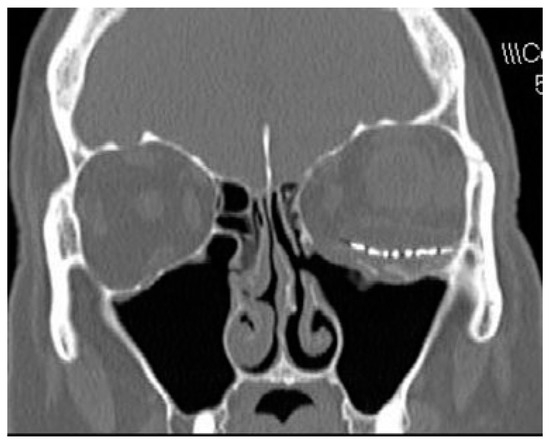

CT scans with coronal and axial views are the imaging modality of choice in suspected orbital fracture cases. On CT scan, subtle medial wall fractures can be detected by comparing the distance from the midline to the medial wall on the injured and uninjured sides. The fractured side will often show a decreased distance in comparison to the unaffected side (Figure 1). However, CT scan may show minimal displacement of the medial wall if the elastic bone returns back to its original position once the deforming pressure is released and the medial wall defect may ‘‘self-seal.’’ Plain film imaging for medial wall fractures is considered obsolete and can only detect less than 50% of fractures [18].

Figure 1. Computed tomographic scan of a patient who had undergone left orbital floor repair with a previously undiagnosed left medial wall fracture. Note distance from nasal septum to medial orbital wall is much reduced com- pared with the right side.